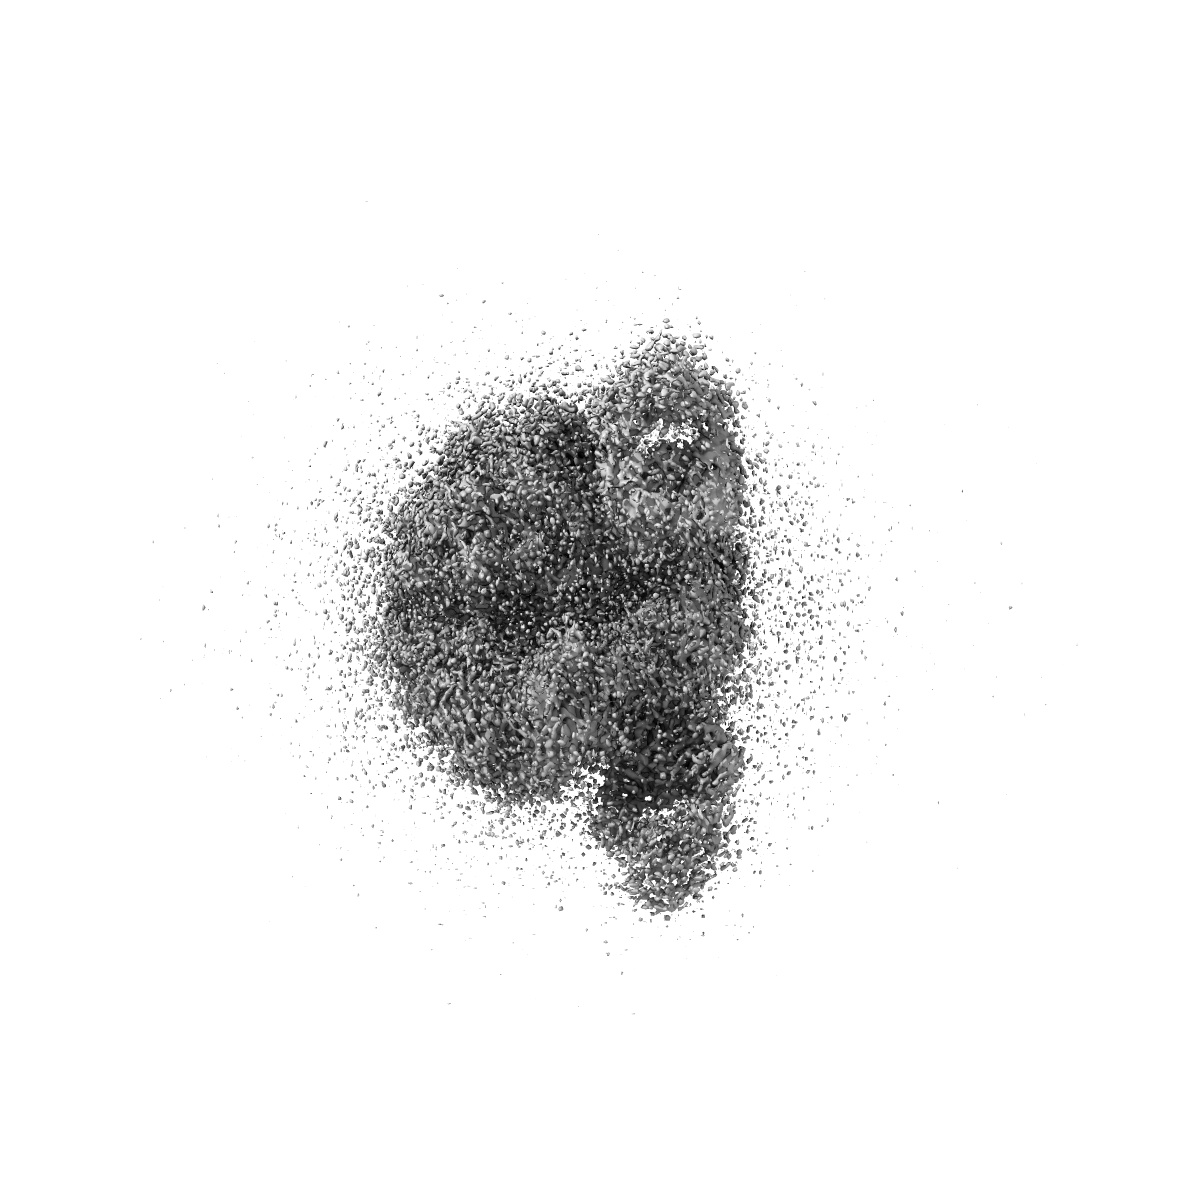

CRYO-EM STRUCTURE OF HIV-1 BG505DS-SOSIP.664 ENV TRIMER BOUND TO DJ85-b.01 FAB

Single-particle3.1 Å

Sample: BG505 DS-SOSIP DJ85-b.01 FAB COMPLEX